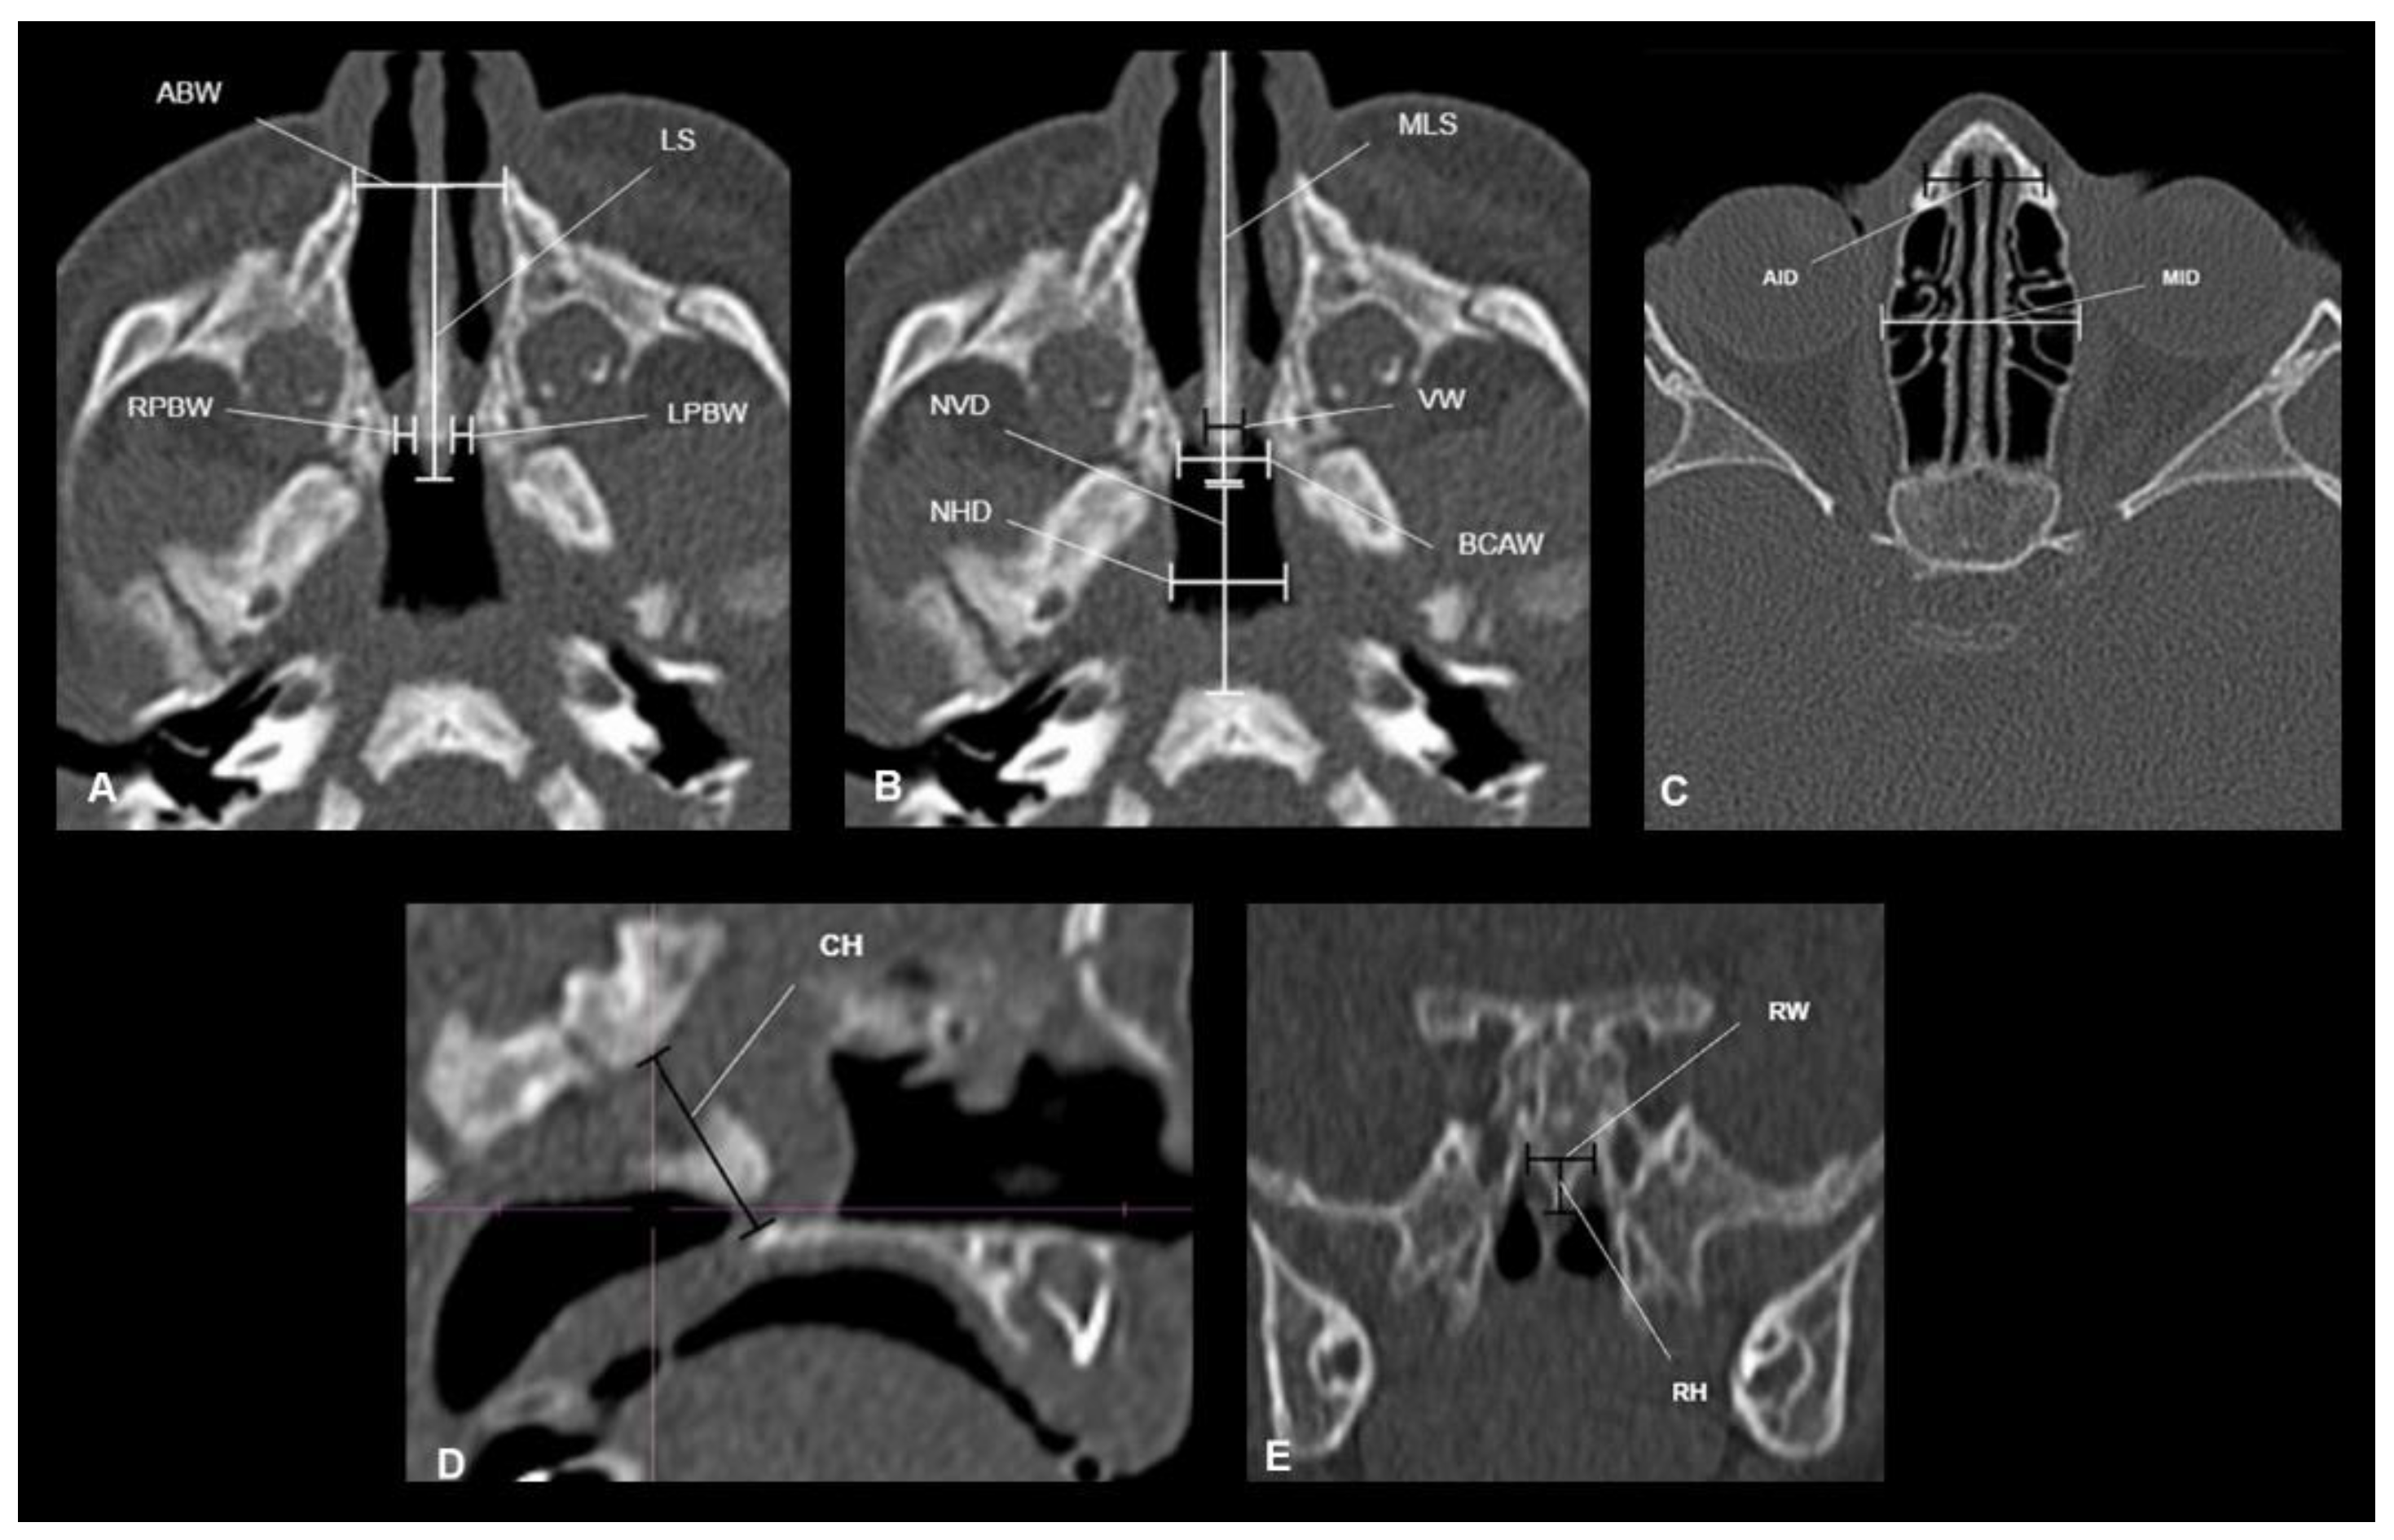

| Measurements | Description |

|---|---|

| Choanal height (CH) | The distance between the horizontal lamina of the palatine bone and the body of the sphenoid |

| Rostrum width (RW) | The maximum width of the sphenoid triangular bone spine. |

| Rostrum height (RH) | The distance between the body of the sphenoid and the junction point of the vomer wings |

| Anterior interorbital distance (AID) | The distance between a point on each tear bone that represents the anterior end of the medial orbital wall |

| Mid Interorbital Distance (MID) | The distance between a point on each medial wall of the bone orbit (ethmoid bone) halfway between the torn bone and the base of the optical pillar |

| Septum thickness (VW) | The maximum width of the vomer |

| Septum length (LS) | The distance from the pyriform opening to the rear end of the vomer |

| Maximum septum length (MLS) | The maximum septum length from the most anterior part of the nasal septum to the rear end of the vomer |

| Anterior bone width (ABW) | The distance between the two ridges protruding from the anterior wall of the maxillary bones |

| Bone width of choana (BCAW) | The distance between the two pterygoid processes |

| Posterior right bone width (RPBW) | The distance between the lateral bone wall of the right nasal cavity and the mucosa of the septum |

| Posterior left bone width (LPBW) | The distance between the lateral bone wall of the left nasal cavity and the mucosa of the septum |

| The vertical distance of the nasopharynx (NVD) | The distance between the rear vomer and the base of the skull |

| Horizontal nasopharynx distance (NHD) | The distance between the middle third of the nasopharyngeal sidewalls |